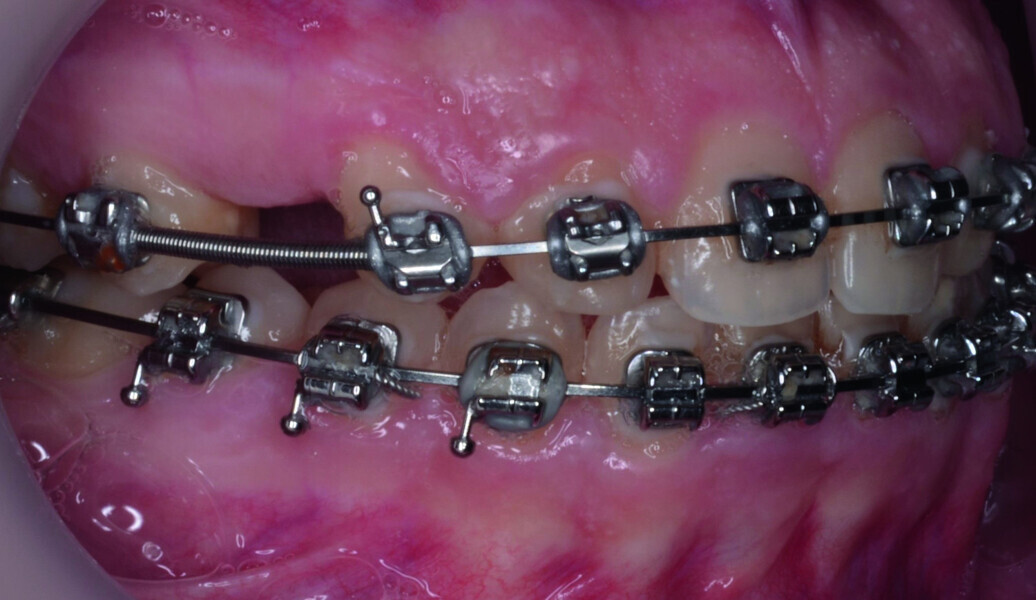

Orthodontic management of maxillary lateral incisors agenesis